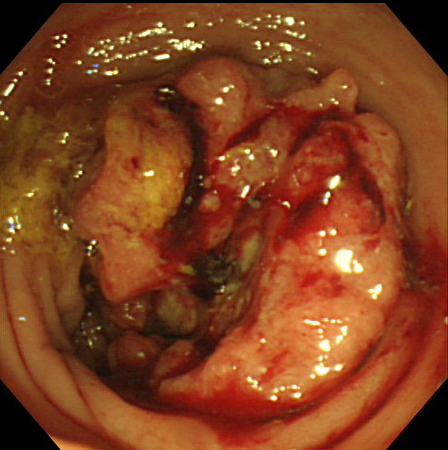

大腸ポリープと大腸がん

大腸内視鏡検査を行った結果、「大腸がん」はないけれど「大腸ポリープ」があったという方が多くいます。実際に大腸ポリープは便潜血陽性で内視鏡検査を行った方の4人に1人程度で見つかるとされています。大腸ポリープは大腸がんの原因となるものです。正常な細胞が増殖するときに遺伝子のコピーミスが起きるとポリープが発生し、そこからさらにコピーミスが発生すると癌ができるといわれています。

このようなポリープの中から大腸がんができてくる